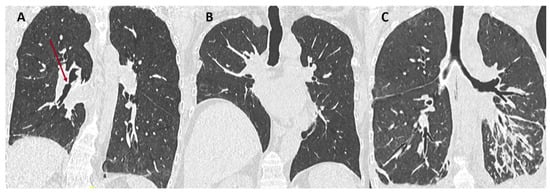

7. When to Perform a CT Scan in the Setting of CLAD